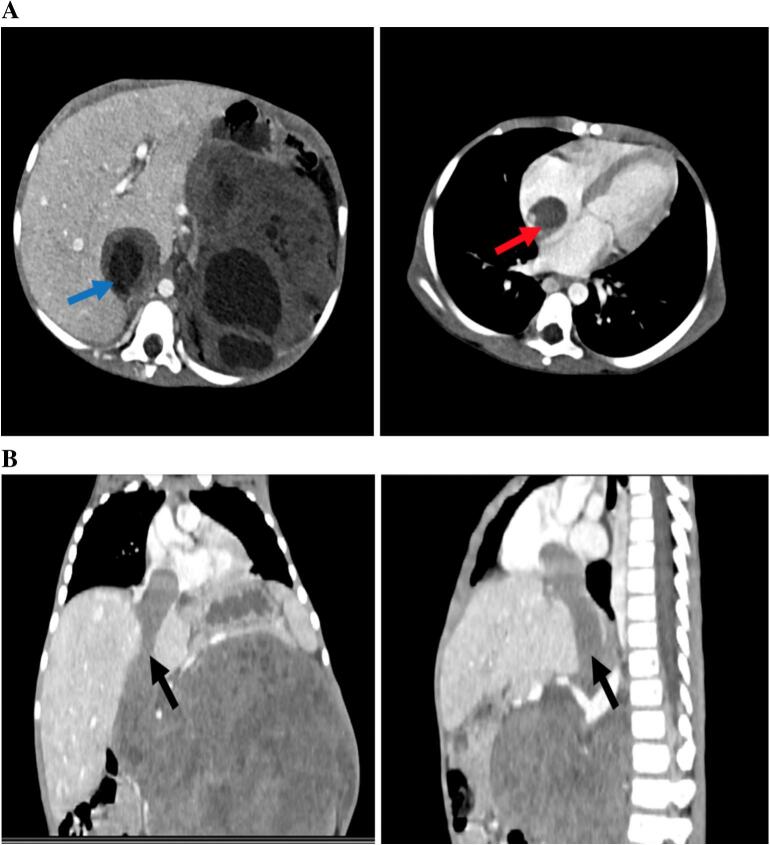

Case presentation: Herein a rare case of a 3-year-old boy presenting with a giant Wilms tumor exhibiting extensive intravascular spread. Preoperative CT scans of the chest and abdomen revealed significant invasion into the IVC with thrombus extending into the right atrium. The patient underwent neoadjuvant chemotherapy, which led to marked tumor and thrombus reduction. Intraoperatively, the tumor was found adherent to the colon and left common iliac artery but was dissected without arterial injury. A massive intravascular thrombus was identified, forming a wandering thrombus, with evidence of collateral venous drainage indicating longstanding IVC obstruction. Cavotomy was performed, and the IVC was completely transected without hemodynamic compromise due to collateralization. The surgery was uneventful, and the patient recovered in the Pediatric Intensive Care Unit (PICU).